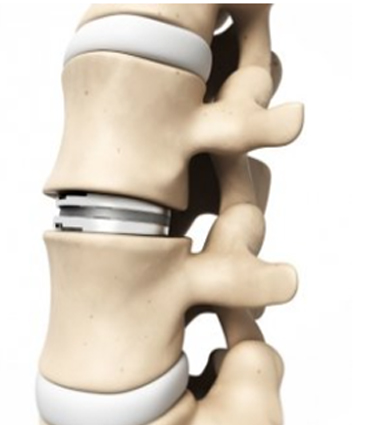

Artroplastia Cervical